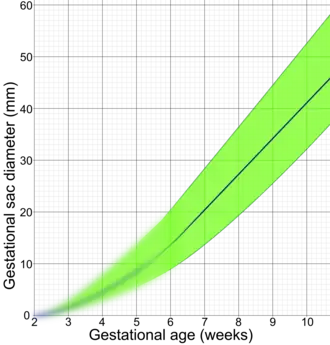

De gemiddelde vruchtzakdiameter[9] kan de postmenstruele leeftijd van de zwangerschapsduur effectief schatten[10] tussen de 5 en 6 weken, met een nauwkeurigheid van ongeveer +/- 5 dagen.[11]

De dooierzak en embryo zijn gemakkelijk herkenbaar, wanneer de vruchtzak een bepaalde grootte heeft bereikt; een dooierzak is voor het eerst te zien als de vruchtzak 20 mm is en de foetale pool als de vruchtzak 25 mm groot is.

Crown-rump length before a gestational age of 6 weeks is extrapolated by assuming a gestational sac diameter of 0 at a gestational age of 2 weeks, corresponding to a fertilization age of 0 weeks. This extrapolated part is blurred because of uncertain values. - ↑ Mean sac diameter | Radiology Reference Article | Radiopaedia.org. Radiopaedia. Geraadpleegd op 2 October 2021.